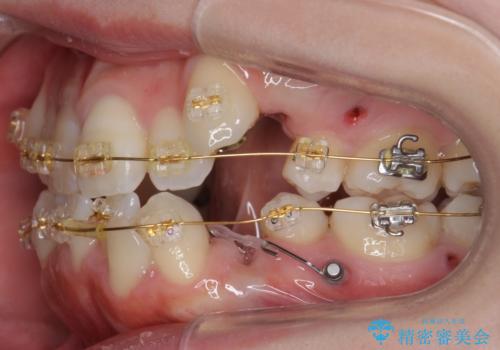

- 前歯のがたがたを主訴に来院。

八重歯と、前歯のやや開咬の症状もあり難易度としては中等度でした。

上下左右の小臼歯を抜歯し、ワイヤー矯正を行いました。

犬歯のコントロールが難しく、矯正用ミニスクリューを併用しました。

奥歯の歯の間が狭く、ミニスクリューを入れるのも難しい症例でした。